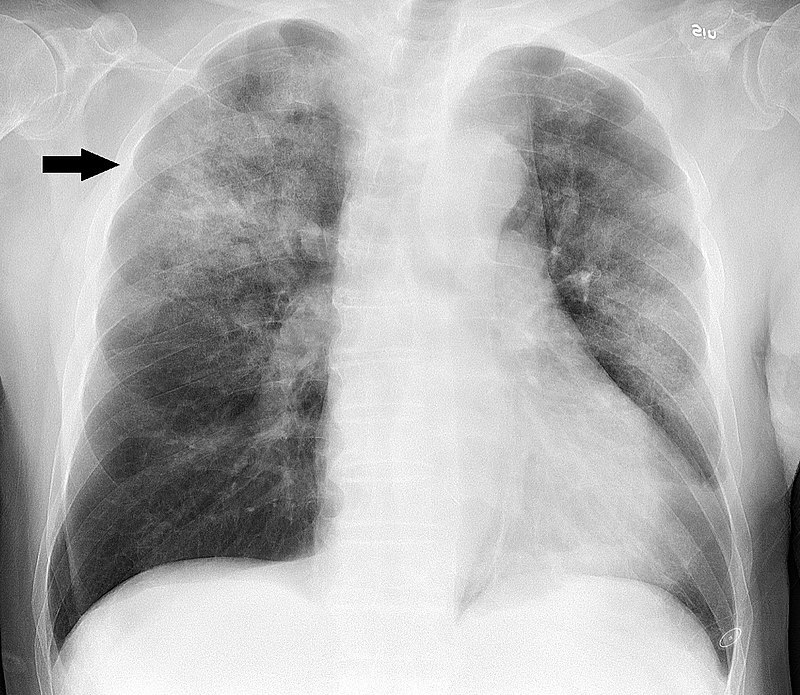

What investigations can you do for Brochitis if you sus Pneumonia instead?

When is this indicated? (4 things)

CXR

Indicated if you have Pneumonia signs:

- Fever

- Tachypnea

- Dullness to percussion (consolidation)

- Tactile fremitus (louder 99) (consolidation)

What will you see in a CXR that you requested in sus Bronchitis but you acc sus Pneumonia?

If bronchitis = normal CXR

If pneumonia = consolidation